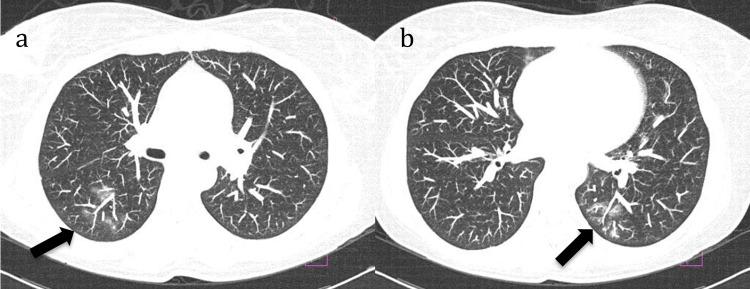

Rituximab, a chimeric monoclonal antibody targeting the CD20 antigen on B cells, is widely used in oncological and immune-mediated diseases. However, late-onset neutropenia can occur, even in patients receiving concomitant immunosuppressants or chemotherapeutics, necessitating therapeutic adjustments. The development of neutropenia with rituximab monotherapy reinforces the relationship, but the exact pharmacological mechanism is still unknown. We report two cases of late-onset neutropenia after rituximab therapy: the first case is related to a woman with rheumatoid arthritis and anti-neutrophil cytoplasmic antibodies (ANCA)-associated vasculitis overlap and a history of alveolar hemorrhage; the second case concerns a woman with systemic lupus erythematosus and neurological manifestations. Both patients were hospitalized for febrile neutropenia, an unusual complication, and subsequently recovered after treatment with antibiotics and granulocyte colony-stimulating factor. Rituximab was discontinued. It is essential for rheumatologists to recognize and monitor for late-onset neutropenia during and after rituximab treatment, as early detection and intervention can prevent severe complications. The heterogeneity in clinical course observed in reported cases underscores the complexity of the condition and the impact on patient safety. The feasibility of resuming rituximab treatment after late-onset neutropenia requires careful evaluation.

利妥昔单抗是一种靶向B细胞上CD20抗原的嵌合单克隆抗体,广泛应用于肿瘤学和免疫介导性疾病。然而,即使是接受联合免疫抑制剂或化疗药物治疗的患者,也可能发生迟发性中性粒细胞减少症,这就需要进行治疗调整。利妥昔单抗单药治疗导致中性粒细胞减少症的发生强化了这种关联,但确切的药理机制仍不清楚。我们报告了两例利妥昔单抗治疗后发生迟发性中性粒细胞减少症的病例:第一例是一位患有类风湿关节炎和抗中性粒细胞胞浆抗体(ANCA)相关血管炎重叠且有肺泡出血病史的女性;第二例是一位患有系统性红斑狼疮并有神经系统表现的女性。两名患者均因发热性中性粒细胞减少症这一不寻常的并发症住院,随后经抗生素和粒细胞集落刺激因子治疗后康复。利妥昔单抗停药。风湿病学家在利妥昔单抗治疗期间和治疗后识别并监测迟发性中性粒细胞减少症至关重要,因为早期发现和干预可预防严重并发症。报告病例中观察到的临床病程异质性突出了该病症的复杂性及其对患者安全的影响。迟发性中性粒细胞减少症后恢复利妥昔单抗治疗的可行性需要仔细评估。